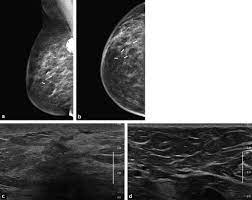

What Does Inflammatory Breast Cancer Look Like On Ultrasound / Benign And Malignant Characteristics Of Breast Lesions At Ultrasound Radiology Reference Article Radiopaedia Org : Ultrasound is useful for looking at some breast changes, such as lumps (especially those that can be felt but not seen on a mammogram) or changes in women with dense breast tissue.. Unlike typical breast cancer, ibc usually cannot be detected by a mammogram or ultrasound. What does breast cancer look like on a mammogram? Inflammatory carcinoma of the breast, also referred to as inflammatory breast cancer, is a relatively uncommon but aggressive form of invasive breast carcinoma with a characteristic clinical presentation and unique radiographic appearances. I need some knowledge about ibc. My last breast ultrasound was december.

It's called inflammatory because that's how it looks. Any area that does not look like normal tissue is a possible cause for concern. Inflammatory breast cancer, also known as carcinomatous mastitis, t4d, or pev 2 or 3, is the only real therapeutic emergency in breast oncology, given the high risk of metastasis, the reason for the most unfavourable prognosis of all breast cancers.it must consequently be diagnosed rapidly, and imaging examinations must in no case delay therapeutic management. Because ibc grows quickly, it is usually found at a locally advanced stage, meaning that cancer cells have spread into nearby breast tissue or lymph nodes. A breast ultrasound is a scan that uses penetrating sound waves that do not affect or damage the tissue and cannot be heard by humans. Ultrasound is useful for looking at some breast changes, such as lumps (especially those that can be felt but not seen on a mammogram) or changes in women with dense breast tissue. As these inflammatory breast cancer picture shows, the texture of the breast may change and appear to look dimpled or ridged, like an orange peel. Their differences, however, lie in their enhancement.

However, inflammatory breast cancers are more likely to show solid mass lesions. The problem is that inflammatory breast cancer can look very much like mastitis early on, and is often diagnosed only after a woman has been treated first for mastitis (often with no improvement in symptoms). This condition usually does not develop a lump, but commonly affects the breast skin. The aim of this study was to evaluate the features of inflammatory breast carcinoma (ibc) on mri compared with mammography and ultrasound and to better define the role of mri in patients with this aggressive disease. These tubes, which are hollow, allow lymph fluid to drain out of the breast.

Rapid onset of symptoms (redness, swelling, warmth, itching, skin thickening) are hallmarks of the disease. You can imagine my fear when a red area appeared on my chest. Early warning signs of inflammatory breast cancer along with images of inflammatory breast cancer are mentioned below. However, inflammatory breast cancers are more likely to show solid mass lesions. The aim of this study was to evaluate the features of inflammatory breast carcinoma (ibc) on mri compared with mammography and ultrasound and to better define the role of mri in patients with this aggressive disease. I need some knowledge about ibc. My last breast ultrasound was december. I know imaging doesn't show ibc.